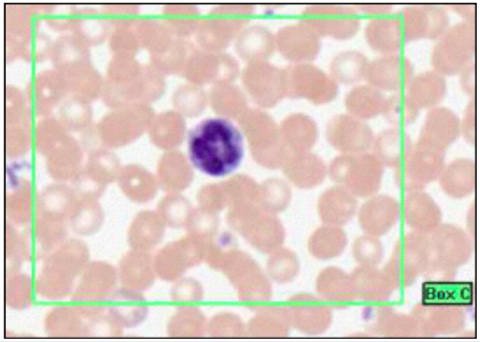

LYMPHOCYTES

- small cells with dark stained nucleus and little cytoplasm

- B and T are indistinguishable

- immature are bigger than RBC, smaller than granulocytes

- mature roughly equal size to granulocyte